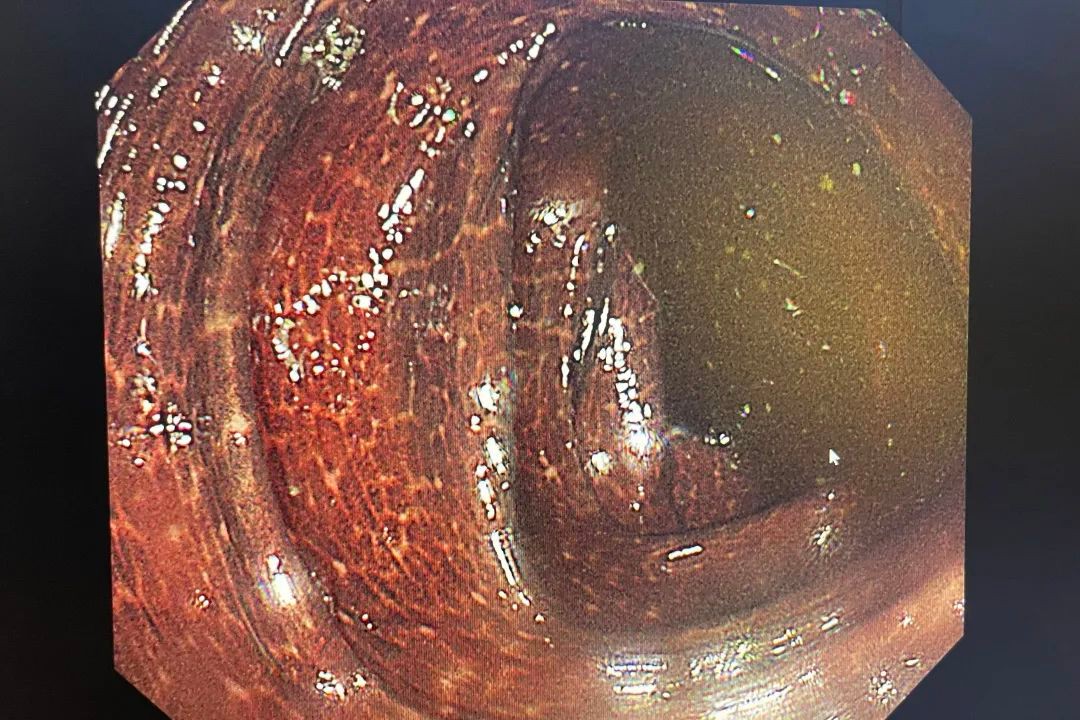

速豹新闻网淄博讯(记者 叶涛 苗露 通讯员 于雪松)4月5日起,世博高新医院开展结肠癌早癌免费筛查活动。据悉,随着人民生活水平的不断

2022-04-07